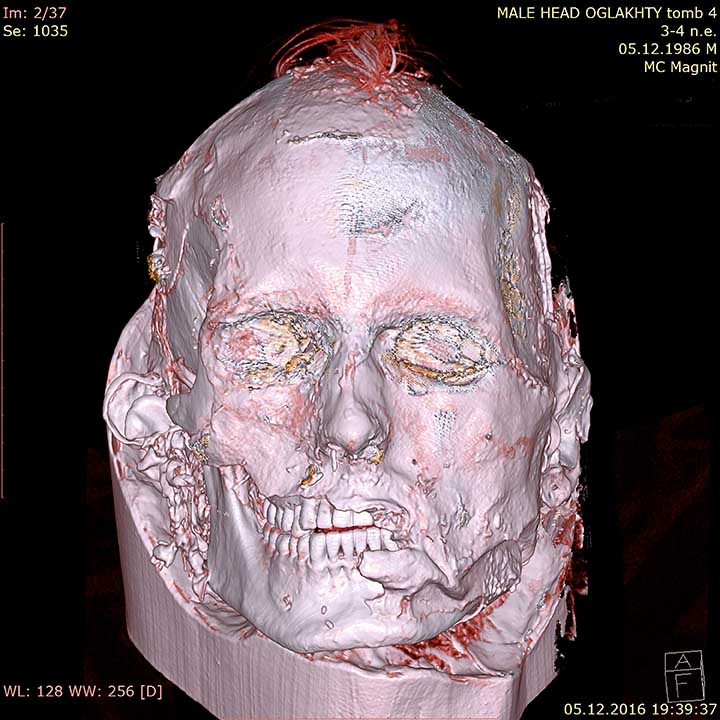

The scan gives it a red punk look but it is believed that the pigtail it was wearing would have been taken off before his death. He is also the only Tashtyk mummy so far found with tattoos. But the most striking and unexpected aspect is a long suture on the side of his face: from the left eye to the ear.

A scar that had been sewn up.

Archaeologists want more research on this but the current best guess is that this suture was stitched after his death – perhaps to mend his disfigured face after a wound, possibly a fatal blow. In other words, to improve his looks before his journey to the afterlife. Final confirmation is still needed that this facial embroidery was postmortem, however. For now, it is not ruled out that this repair job was done at the end of his life.

Nor was this the only evidence of intervention by ancient surgeons on this Tashtyk man found at the Oglakhty burial ground, and laid to rest in a burial log house. His skull was trepanned in the temporal area on the left side,’ explained Dr. Svetlana Pankova, curator at the State Hermitage Museum, St Petersburg, and keeper of the Siberian collection of the Department of Archeology.

The hole is rather big – 6 by 7 centimetres. It was made postmortem. Expert analysis shows the hole was made by the series of blows with a chisel type or hammer type tool.’ Dr Pankova said: ‘We think that it was made to remove the brain during an elaborate burial rite.’ Likewise, she thinks the facial scar can be explained in similar fashion.

‘Our research is complicated by the fact that we cannot take the mask away from the face (it would cause too much damage) so we must research this stitching using other methods. The archaeologists were intrigued to finally see the face under the death mask, the painting of which ‘adds some unnecessary emotional impressions’

‘The computer scan allowed us to see, so to say, three layers – the layer of the mask, the layer of the face without the mask and layer of the skull.’ The face of the woman lying in the same burial chamber – also buried in a fur coat – has not been revealed with a CT scan.